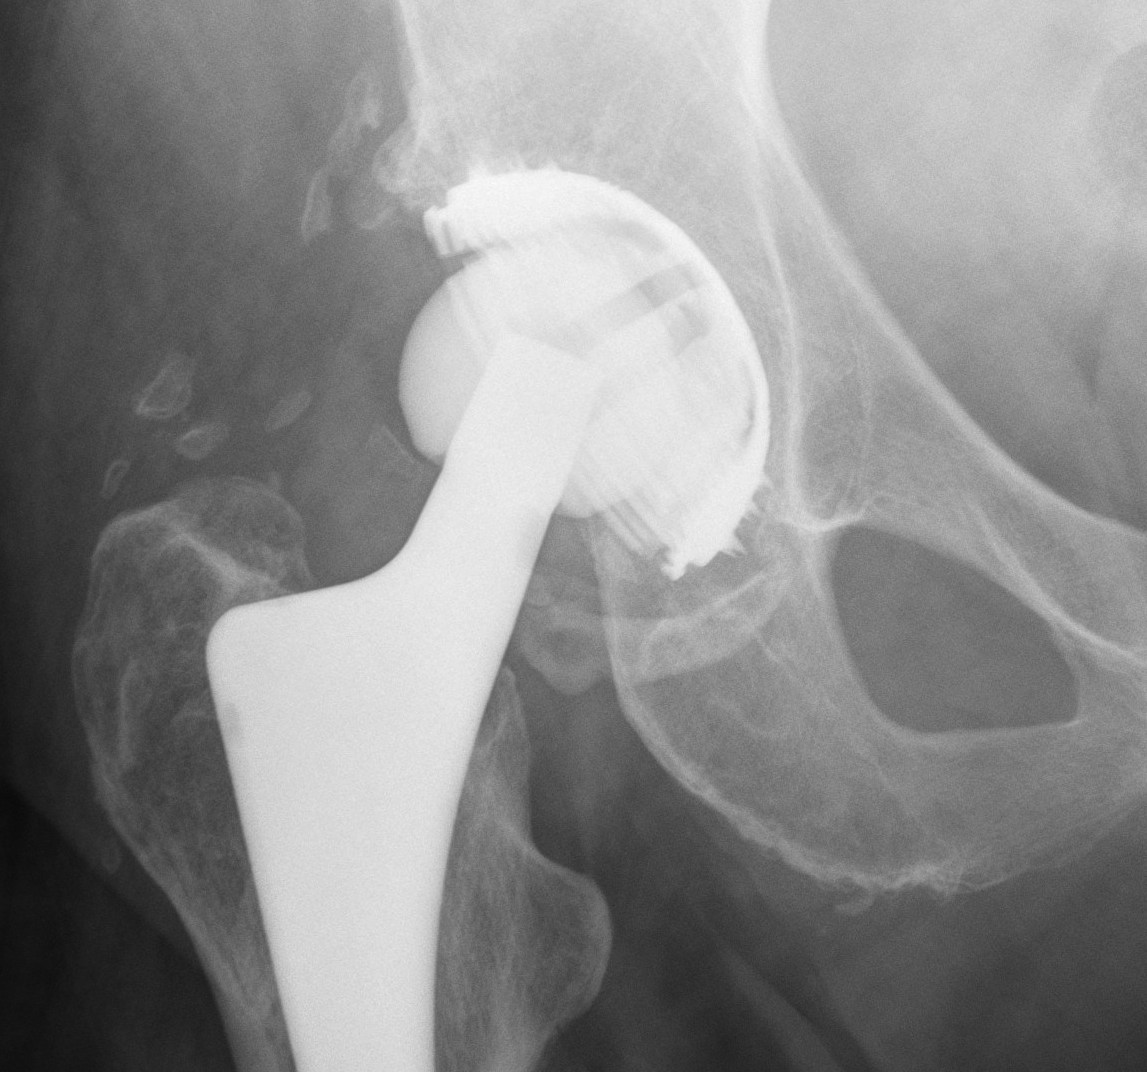

Uncemented Acetabular Component

Concepts

Bone ingrowth into component averages only 12%

- even with 84% bone contact

Non continuous radiolucent lines

- commonly found in press fit acetabular components

- are often not progressive

Radiographic signs of ingrowth fixation

Moore et al CORR 2006

- 3 or more 97% stable

- 2 or less, 83% unstable

Five signs

- absence of radiolucent lines

- presence of a superolateral buttress

- medial bone stress-shielding

- radial trabeculae

- inferomedial buttress

THR Uncemented Cup Superolateral Buttress 2

Radiographic signs of loosening

5 signs

- radiolucent lines that appear after two years

- progression of radiolucent lines after two years

- radiolucent lines in all three zones

- radiolucent lines 2 mm or wider in any zone

- migration > 2mm

Loose Uncemented CupLoose Uncemented Cup 2